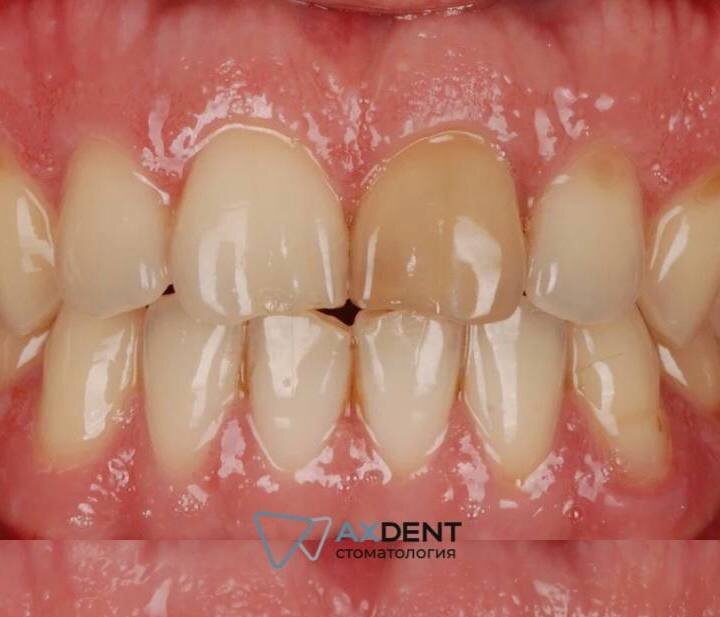

Если обобщить, то проблема всегда выглядит так: все зубы как зубы, а один выделяется вызывающей серостью. Особенно это удручает, если зуб находится в видимой области улыбки. И если бы не он один такой “серенький волчок”, то улыбка смотрелась бы на порядок привлекательнее.

Проводить комплексное отбеливание в таком случае бесполезно: темный зуб останется темным, потому что его цвет продиктован не внешними факторами. Это сигнал изнутри. Проблема — не на поверхности эмали, а в глубине зуба, в его «сердце» — дентине.

Вы упали с велосипеда, не надели капу во время тренировки по боксу или просто сразились со столбом. Зуб перестает болеть, но спустя время он меняет цвет, что может указывать на повреждение нервно-сосудистого пучка. При некрозе пульпы прекращается питание тканей, сосуды, нервы, гемоглобин распадаются, а продукты распада проникают в дентинные канальцы, буквально пропитывая их. Получаем тусклый зуб серо-синюшного оттенка. Эмаль при этом может быть идеальной, но сквозь нее просвечивает темный, измененный дентин. Осветлить такой зуб — это как пытаться отбелить стекло, за которым висит черная шторка. Бесполезно. Нужно работать с источником цвета.